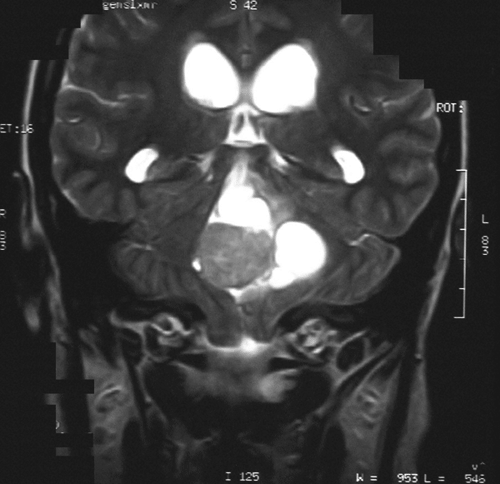

On T1-weighted MR image (Panel A) with gadolinium enhancement, there is a midline cystic lesion with a well-demarcated, oval, mural nodule that has smooth margin. The nodule seems to have a thin and brightly enhancing rim. The core of the nodule shows heterogeneous enhancement. On T2-weighted MR image (Panel B), the nodule is hyperintense to the grey matter and is heterogeneous. No significant edema is demonstrated in the parenchyma surrounding the tumor.

The brain invasion without association with edema that can be demonstrated on T2-weighted MR image is a small surprise.   Although the morphologic features are suggestive of choroid plexus papilloma, the possibility of a metastatic low-grade carcinoma has been entertained during intraoperative consultation.

CT scan demonstrates a homogeneously hypodense to slightly hyperdense enhancing mass with or without cyst area and secondary hydrocephalus. High density on CT within the tumor may represent calcification or blood. Homogeneous enhancement on contrast-enhanced CT is typical due to the marked vascularity of these tumors. The appearance of a CPP on MRI  is similar to that of a CT scan and shows intermediate-to-strong intensity on both T1- and T2-weighted images 2, 3, 4.